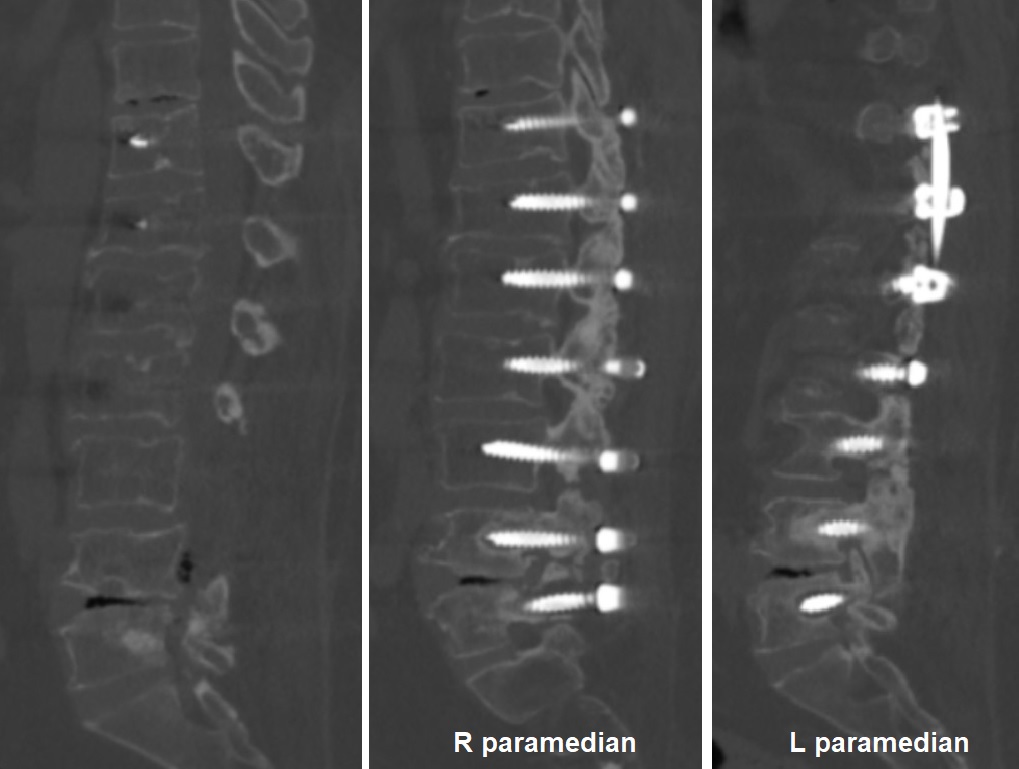

2022 Yılı MRG İncelemesi ve Myelografi

Resim 2: Yaptırılan MRG incelemesinde median, sağ ve sol paramedian kesitler ve MR-myelografi incelemesi görülmekte. Alt seviyelerde santral stenoz yoktur, T10-T11 seviyesi ise şüphelidir. Ancak paramedian kesitlerde T9-T10, T10-T11, L4-5 ve L5-S1 seviyelerinde lateral reses ve foramen stenozları şüphesi vardır. İmplantların artefaktı ideal bir değerlendirmeyi engellemektedir.

2022 Yılı BT İncelemesi - Vida Gevşemesi

Resim 3: BT incelemesinde T10-T11 ve L4-L5 diskleri içinde ve ayrıca kanal içinde L4 korpusu arkasında gaz ile uyumlu hipodansite, L4 ve L5 vidalarında iki yanlı gevşeme ve foraminal stenozlar görülüyor. Ayrıca L3-4 ve L4-5 seviyelerinde faset füzyonlarının tam oluşmadığı görülmekte. Diğer vidalarda gevşeme ya da malpozisyon yoktur.